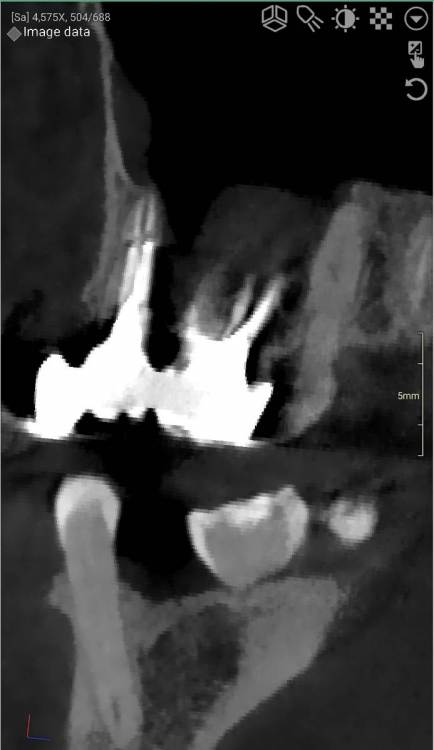

DeLaMer Опубликовано 11 августа, 2021 Поделиться Опубликовано 11 августа, 2021 (изменено) Добрый день уважаемым докторам-участникам форума. Хотелось бы, по возможности, получить экспертное мнение по поводу моей проблемы. На верхней челюсти есть мост, объединяющий 6й, 5й и отсутствующий 4 зубы (если я правильно понимаю нумерацию, это должны быть 24, 25, 26). В начале июня на десне открылся свищ с гноем (абсцесс, но, видимо, не острый, кроме периодического надувания гнойного шарика ничего больше не происходило). По этом поводу мой лечащий врач поднял КТ, которое было сделано осенью до того по другому поводу и обнаружила воспаление одного из корней 6-го зуба. При этом она высказала соображение, что может быть здесь поможет резекция верхушки того самого корня. Один из хирургов, с которым я консультировалась по этому поводу, сказал, что на его взгляд резекция возможна. Другой - что воспаление проявляется не только на одном корне, а на двух и по его мнению сделать тут ничего нельзя, только распиливать коронку и удалять 6й зуб. Я была бы крайне благодарна, если бы уважаемые специалисты высказали свое мнение по этому поводу, потому что при равноценных двух противоположных мнениях мне даже не понятно с чего начинать. Прикрепляю ссылку на файл КТ на своем дропбоксе. Огромное спасибо за помощь https://www.dropbox.com/s/fkv8cvqqq6grgpe/Sergeeva A..zip?dl=0 Изменено 11 августа, 2021 пользователем DeLaMer Ссылка на комментарий

Irouil Опубликовано 12 августа, 2021 Поделиться Опубликовано 12 августа, 2021 По представленным средам создаётся впечатление, что у зуба фактически разрушено соединение между корнями. Риски того, что он под нагрузкой раскроется в любой момент, достаточно высоки Ссылка на комментарий

АнтонТЛТ Опубликовано 13 августа, 2021 Поделиться Опубликовано 13 августа, 2021 (изменено) Там всё ок с фуркацией и вкладка коротконогая. Просто на КТ очень много артефактов. Изменено 13 августа, 2021 пользователем АнтонТЛТ Ссылка на комментарий